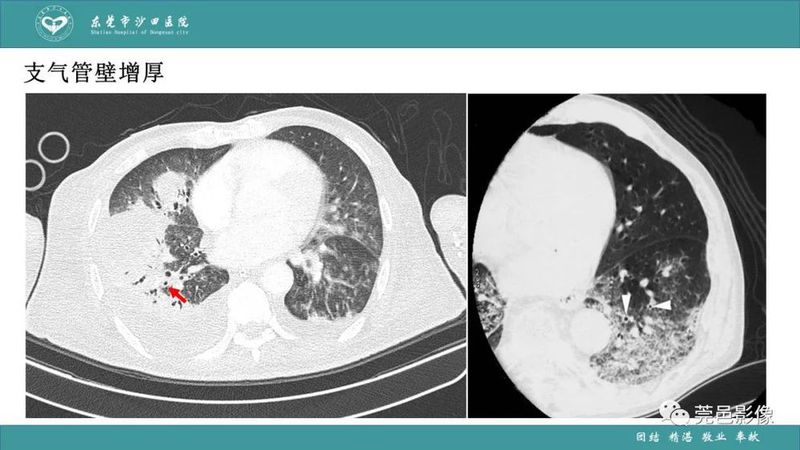

「肺炎克雷伯杆菌肺炎」影像学诊断+鉴别诊断